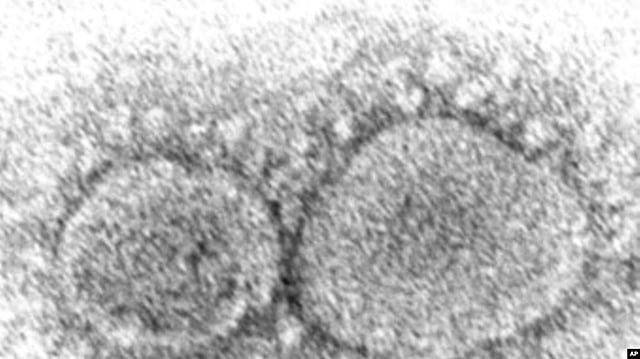

This 2020 electron microscope image made available by the Centers for Disease Control and Prevention shows SARS-CoV-2 virus particles which cause COVID-19. AP